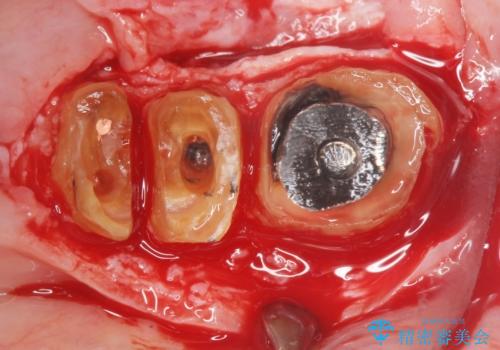

長期的な予後を保証できないことをご了承頂いた上で、歯根分割術、骨外科手術により歯の保存を試みました。

虫歯を丁寧に除去した後に歯根を分割し、骨を削合して健全歯質を露出させる骨外科手術を行いました。

手術後に根管治療を行い、歯肉と骨の治癒を十分に待った後ブリッジによる補綴治療を行いました。